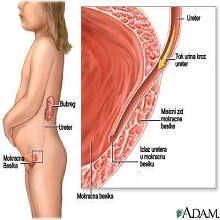

Пијелонефртитис представља запаљење ткива бубрега које траје (бубрежне карлице, чашица и каналића). По дужини трајања дели се на акутни и хронични. |

| Бубрези су парни органи, који представљају централни део уринарног система. Смештени су у ретроперитонеалном простору на задњем зиду абдомена, и налазе се са обе стране кичменог стуба. Десни бубрег, потиснут јетром, постављен је мало ниже у односу на леви. |